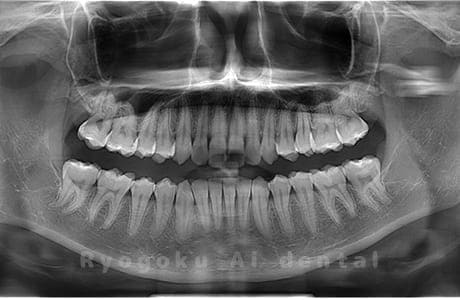

真っ直ぐ生えている親知らず

親知らずが真っ直ぐ生えているタイプです。

このタイプは真っ直ぐ生えていて咬み合わせに問題がなければ、抜歯しないケースもあります。ただし、虫歯になっていたり、痛みがあったり、咬み合わせが悪かったりすると抜歯をおすすめします。